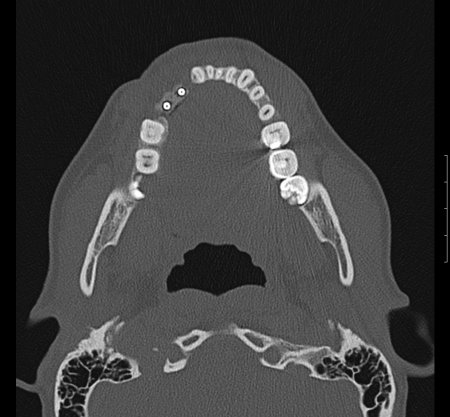

Zur genauen Planung der Kieferkorrektur wurde ich zum CT geschickt. Aus den scheibchenweisen Bildern setzte der Computer ein dreidimensionales Bild zusammen. Dabei ist auch sehr deutlich dieses verlagerte Knochenstück zu sehen.

Zwischenzeitlich stand auch mal die Überlegung im Raum, eine Kinnplastik durchzuführen, bei der die Kinnspitze abgesägt und danach im "richtigen" Winkel wieder aufgesetzt wird. Das klang natürlich auch erst mal ein bissel erschreckend - aber schließlich zählt das Ergebnis. Nach Auswertung der 3-D-Annimation wurde dann allerdings "nur" die erstbeschriebene Kieferkorrektur durchgeführt.